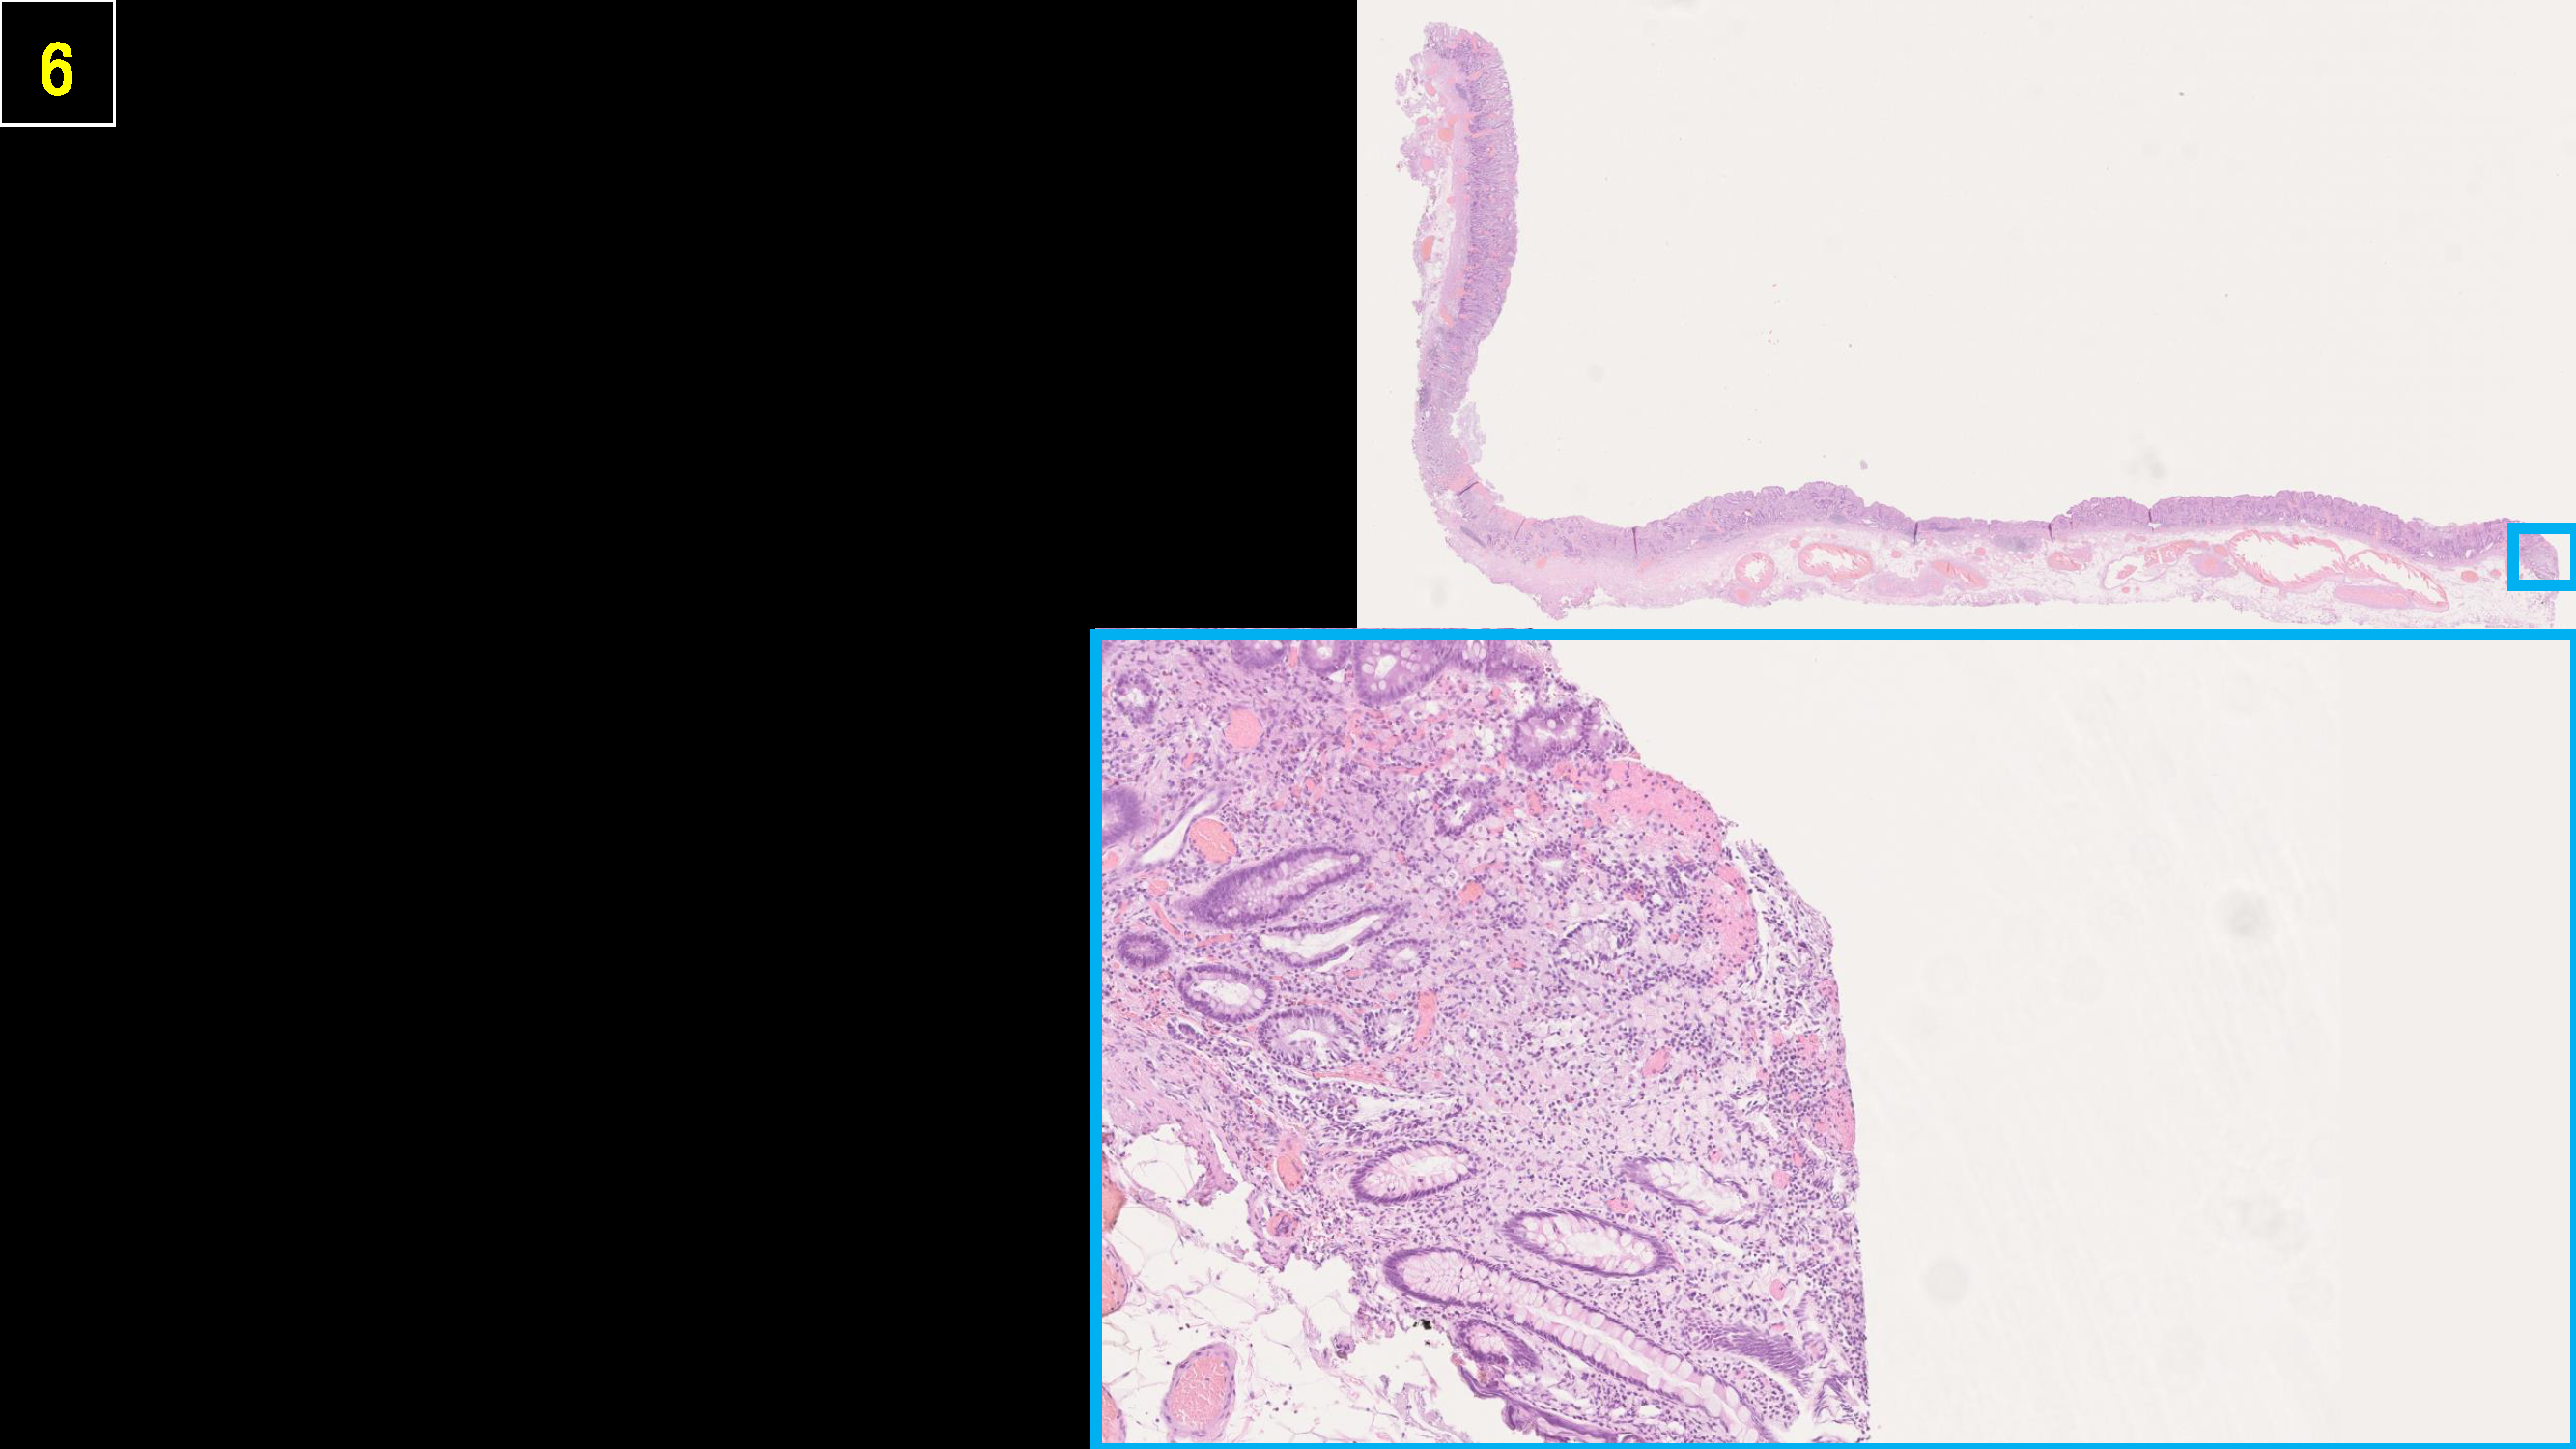

ホーム > 診療科・部門案内 > 消化器センター 消化器内科 > 消化管Mapping > 消化管Mapping~胃~ > 消化管Mapping~胃~ 2025.9.10